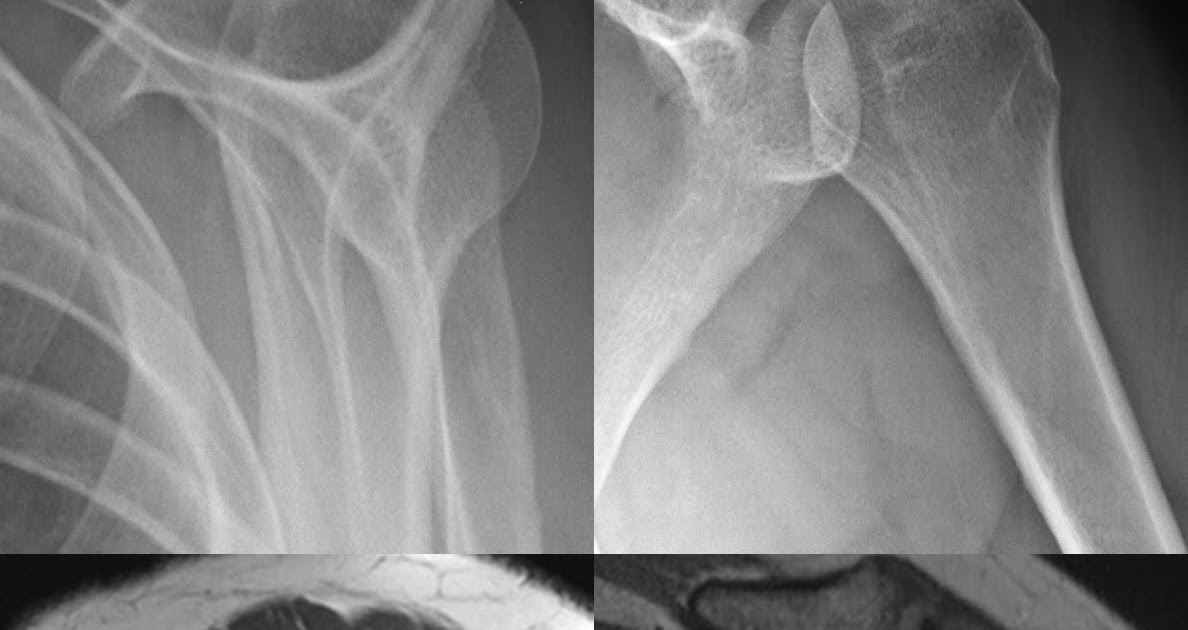

From roentgenrayreader.blogspot.com

Roentgen Ray Reader Calcium Hydroxyapatite Deposition Disease Shoulder Calcium Build Up In Shoulder Joint Calcific tendonitis is caused by calcium build up in your rotator cuff tendons (that attach muscles to the bone). Although this can happen anywhere in the body, it usually occurs in the rotator. The tissues around the deposit can. Even though this condition develops. Calcific tendonitis can occur anywhere in your body, but it most often. Effective treatment can help. Calcium Build Up In Shoulder Joint.